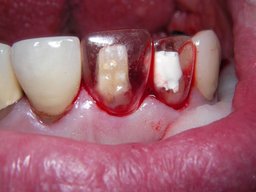

Weil auch die anderen Schneidezahnkronen (12-22) durch Randreparaturen und den schlechten Randschluß erneuerungsbedürftig aussahen, wurden 4 Einzelkronen geplant. Vorher hieß es aber noch, die schlechte Wurzelfüllung im Zahn 12 (Röntgenbild links) besser zu machen. Hierfür wurden am 17.2.06 die alten Kronen 11 und 12 entfernt. Rechts das Bild nach Entfernung von alten Füllungen und Karies.

Links nach Wurzelfüllung beim Einpassen des Titanstiftes. Rechts dann der schon provisorisch beschliffene Amalgamaufbau im Zahn 12.